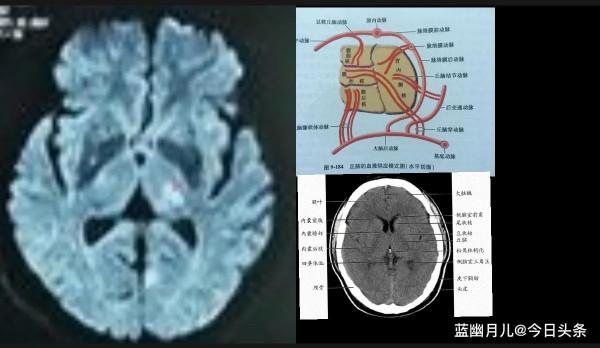

5.腔梗的影像特點

頭顱 CT 可見深穿支供血區單個或多個直徑2一15mm病灶,呈圓形、卵圓形、長方形或楔形腔隙性陰影,邊界清晰,無佔位效應,增強時可見輕度斑片狀強化。以基底節、皮質下白質和內囊多見,其次為丘腦及腦幹。CT 對腔隙性梗死的發現率與病灶的部位、大小及檢查的時間有關。

頭顱 MRI

顯示腔隙病灶呈T1等訊號或低訊號、T2高訊號,T2加權像陽性率幾乎可達100%,並可清晰顯示腦幹病灶。對大腦可行橫斷面、矢狀位、冠狀位掃描,對病灶進行準確定位。能區分陳舊性腔隙系由於腔隙性梗死抑或顱內小出血所致。是最有效的檢査手段。